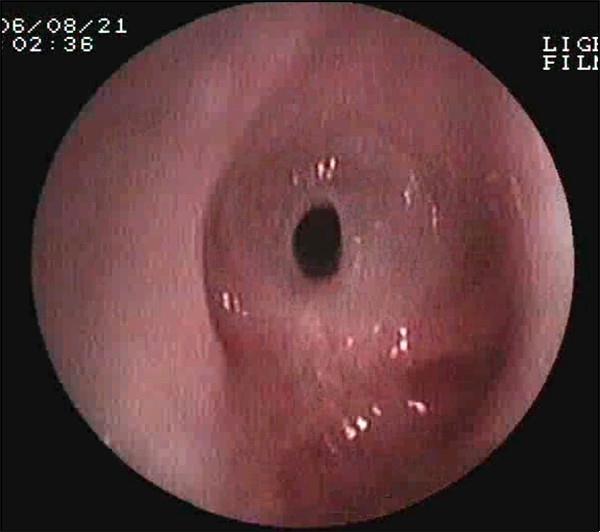

常見的鏡下改變:

氣道狹窄